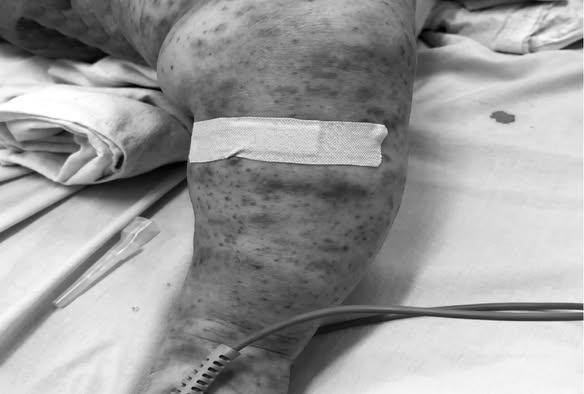

Một bệnh nhân mắc viêm não mô cầu điều trị tại Bệnh viện Bệnh Nhiệt đới TP.HCM

Trong đó thể tối cấp hay còn được gọi là nhiễm khuẩn huyết tối cấp, là dạng nguy hiểm nhất của bệnh. Thể này gây sốc nhiễm trùng, xuất huyết da, suy đa tạng chỉ trong vòng 24 – 48 giờ sau khi khởi phát. Hầu hết các ca tử vong ghi nhận ở Việt Nam trong giai đoạn 2014 – 2023 đều thuộc thể bệnh này, với thời gian tử vong rất ngắn sau khởi phát.

Não mô cầu là bệnh nhiễm trùng cấp tính rất nguy hiểm, có thể gây tử vong trong vòng 24 giờ sau khi xuất hiện triệu chứng